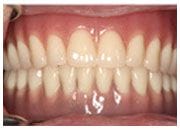

經過本診所細心治療,現在吃東西已經能順利咀嚼,黃女士感謝本診所為它改善飲食上的不便。

治療後